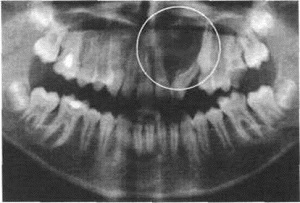

При диагностике остеомиелита челюсти врач осуществляет тщательный осмотр пациента, проводит рентгенодиагностику. Дополнительно необходимо сдать общий и биохимический анализ крови. А для установки возбудителя и проверки его чувствительности к антибиотикам надо сделать бактериологическое исследование гноя из свищей.

В процессе диагностики остеомиелита челюсти врачу важно отделить этот диагноз от других, которые имеют схожие симптомы — например, острого пульпита, острого периодонтита, гайморита, абсцесса мягких тканей и т. д. Точная постановка диагноза значительно увеличивает шансы пациента на полное и более быстрое восстановление.